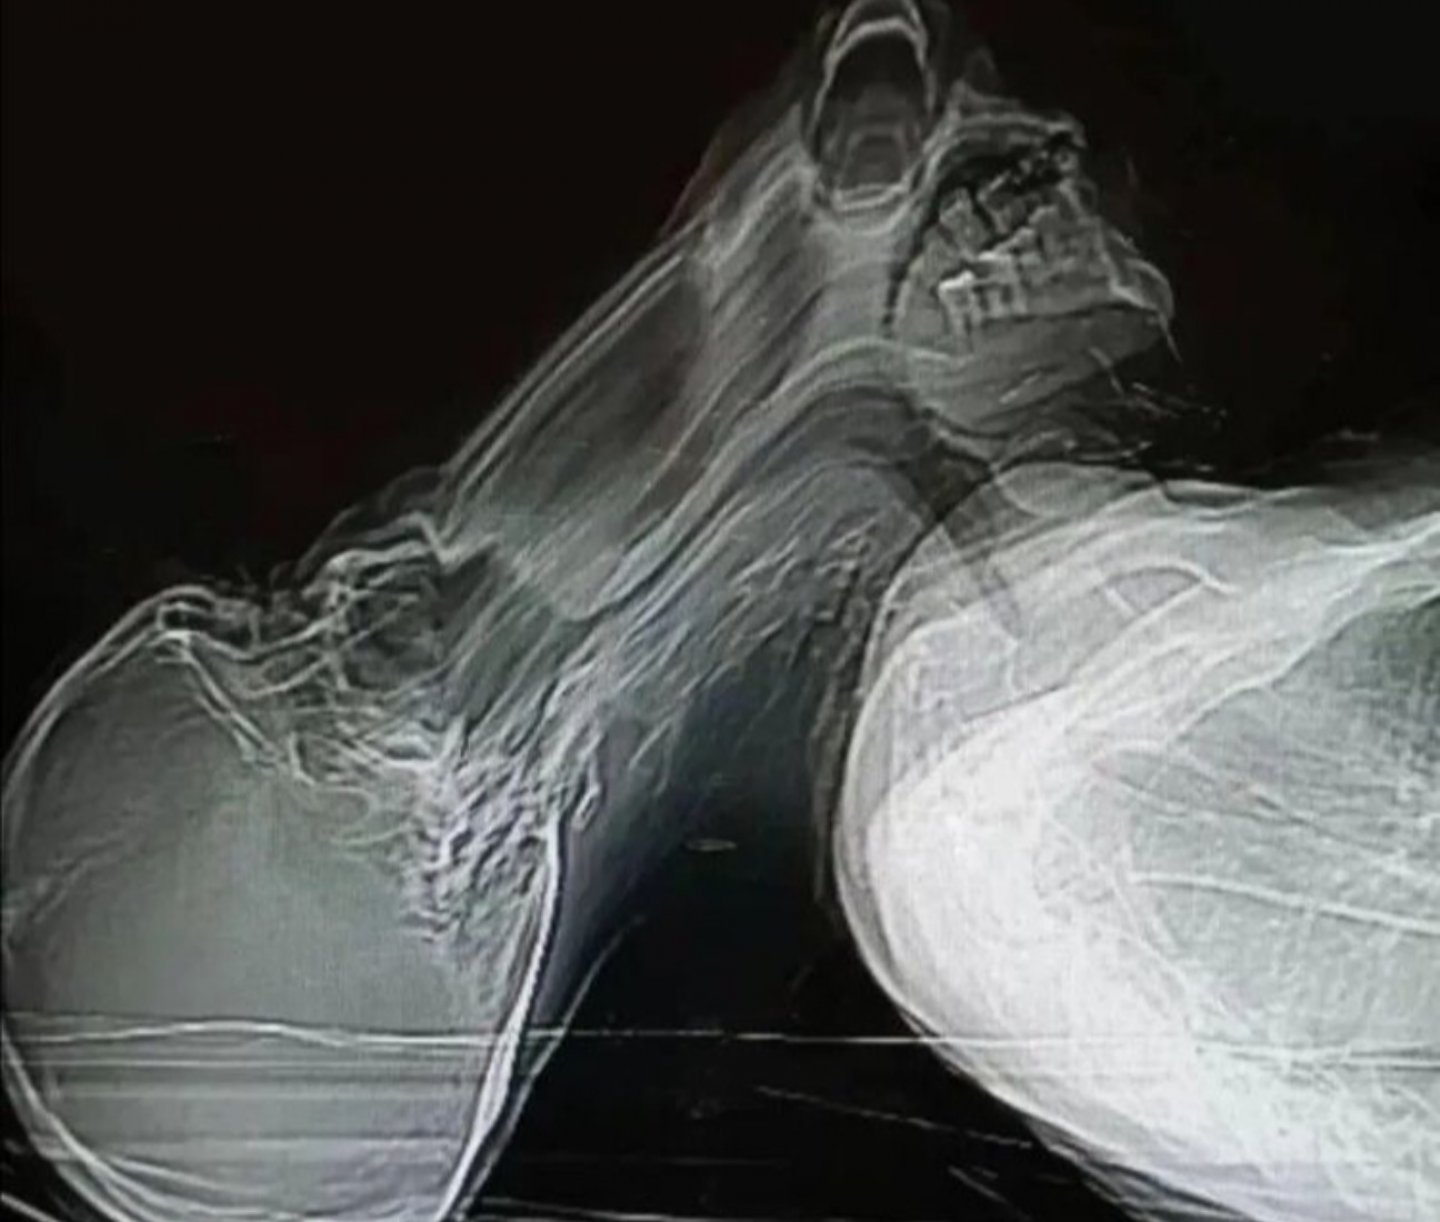

Görsel ilk olarak 20 Ocak’ta Miguel Angel De la Cámara isimli İspanyol bir radyologun Twitter hesabından yanlış bilgi ve sahte haberlerin nasıl oluşabildiğine dair bir örnek olarak paylaşılmış. İspanyolca olarak paylaşılan gönderi dizisinde Miguel Angel De la Cámara bu tür tomografi görüntülerinin nasıl bağlamından koparılıp yanlış bilgi yayılımına neden olabileceğini açıklamış. Söz konusu görselin bir CT taraması olduğunu belirten Miguel Angel De la Cámara, hastanın çekim sırasında uyanıp başını kaldırdığı sırada bu görüntünün oluştuğunu açıklamış.

Bu paylaşımdan sonra örnek olarak paylaşılan görüntü ironik şekilde birçok farklı dilde ruhların varlığına kanıt ya da panik atak geçiren bir kişinin tomografi görüntüsü gibi iddialar şeklinde paylaşıldı.

Bir Twitter hesabı tarafından yapılan paylaşımdaki görselin tomografi sırasında panik atak geçiren bir hastaya ait olduğu iddia edilmişti. Söz konusu tomografi görseli radyolog Miguel Angel De la Cámara tarafından Twitter’da paylaşılmış. Miguel Angel De la Cámara çekim sırasında hastanın uyanması ve başını kaldırmasıyla bu görüntünün kaydedildiğini de belirtmiş. Fakat tomografi görüntüsü bağlamından koparılarak birçok mecrada paylaşılmış.